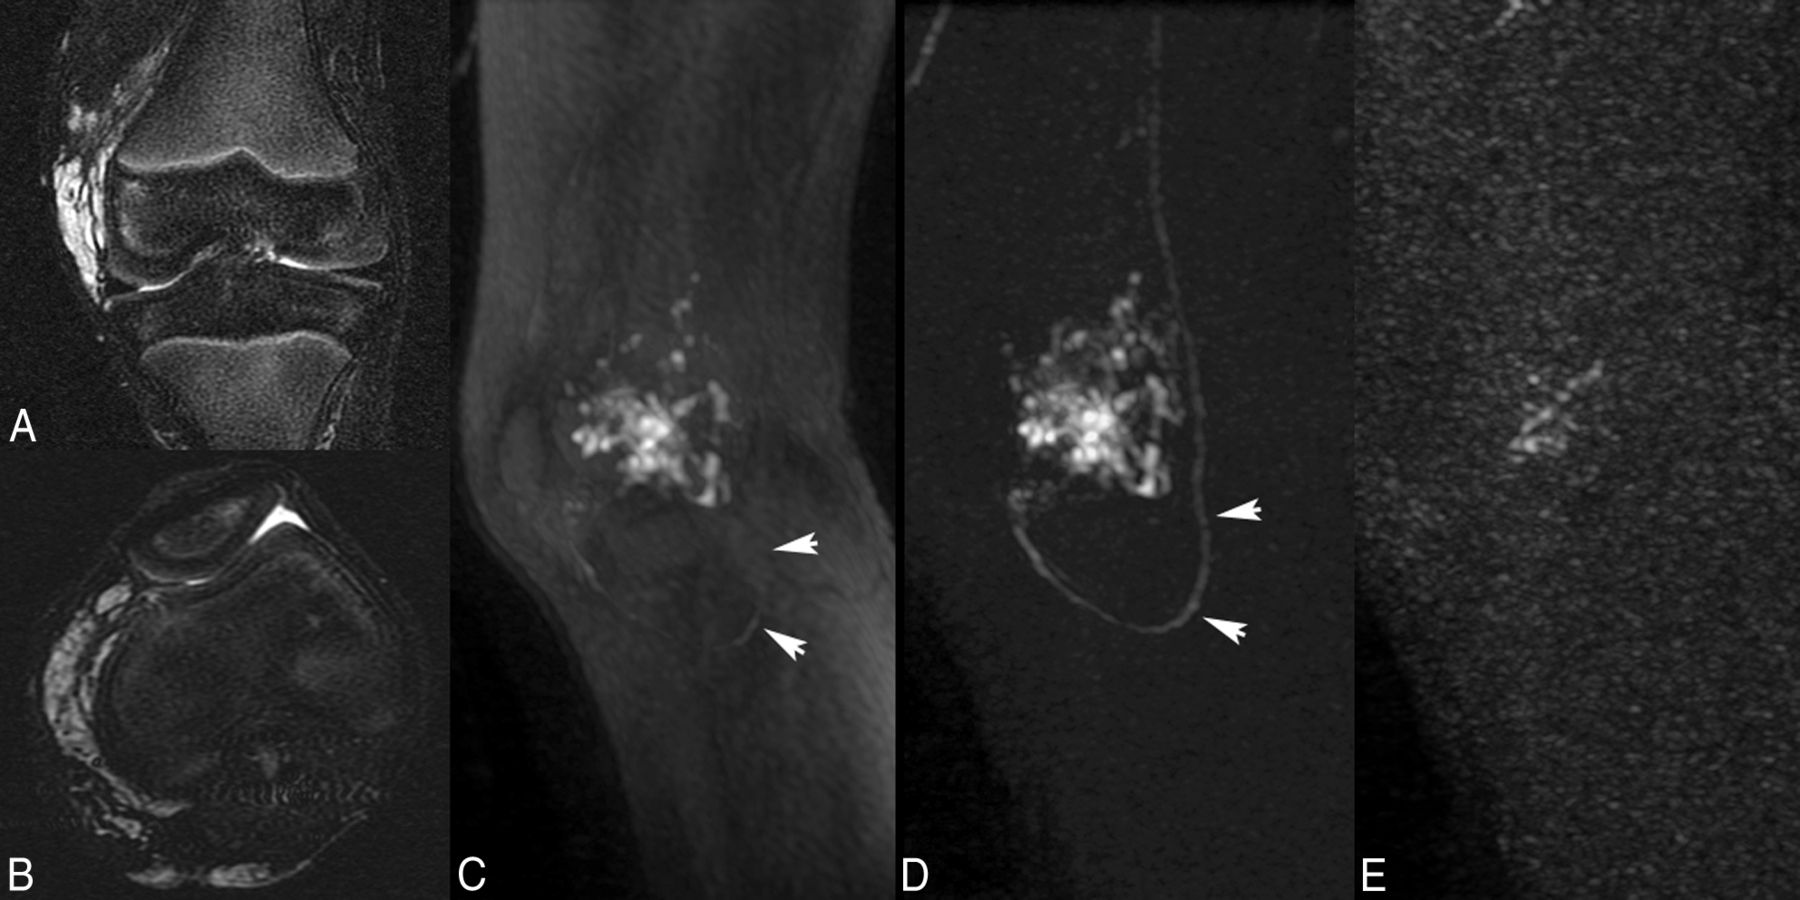

A 6-year-old boy with a peripheral venous malformation of the left knee. Note depiction of the mask subtraction technique that results in more complete visualization of the vascular structures on MR angiography. Coronal (A) and axial (B) T2-weighted fat-saturated MR images demonstrate a multiloculated increased T2-signal venous vascular malformation in the left knee, particularly surrounding the medial and posterior portions of the distal femur. Pretreatment MR angiogram, without (C) and with (D) digital mask subtraction, shows opacification of the venous malformation but limited visualization of the draining vein (arrowheads) without mask subtraction; however, there is not only improved visualization of the venous malformation but also excellent visualization of the draining vein (arrowheads) achieved following mask subtraction of the images. E, Posttreatment MR angiogram again shows pruning of the vascular channels of the venous malformation with no significant flow into the draining vein, compatible with satisfactory embolization of the lesion.